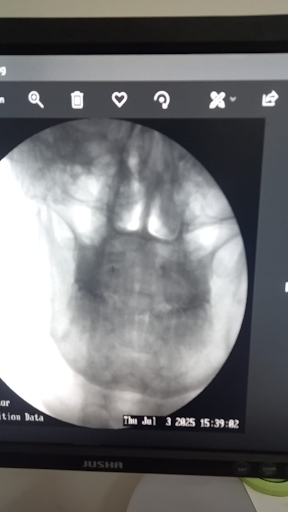

- Dynamic X-rays (flexion-extension views).

- Fluoroscopy to observe real-time instability.